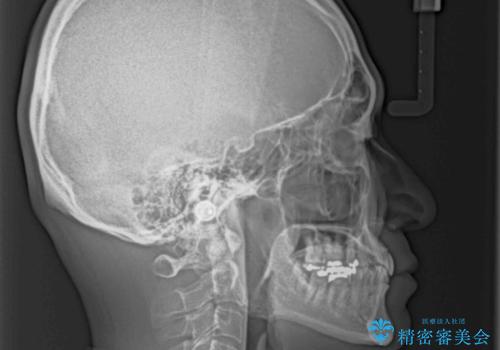

下顎前歯が隠れるほどのディープバイトにより、強い咬合力と突き上げで上顎歯列に隙間が空いている状態でした。

手前に傾斜している奥歯をワイヤー装置で立ち上がらせ、咬み合わせの高さを挙上することで突き上げを解消し、空隙歯列を改善していくこととしました。